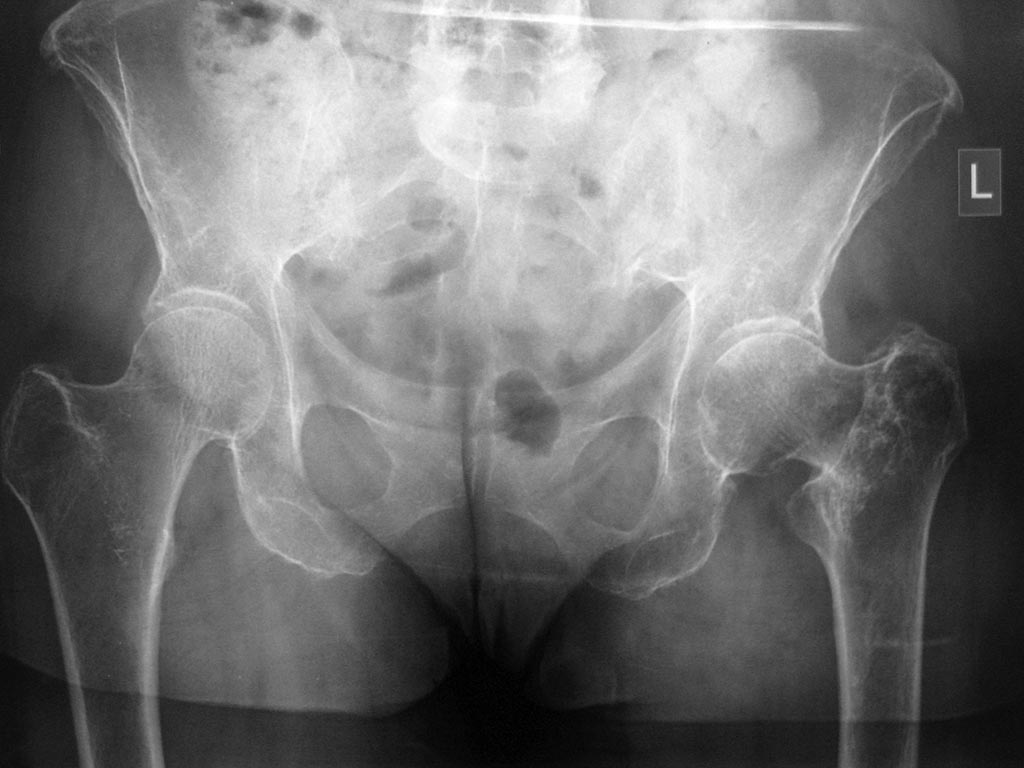

Добрый день! Обратилась женщина, 66 лет, лечится стационарно в неврологическом отделении по поводу болей в поясничном отделе позвоночника. В декабре получила чрезвертельный перелом левого бедра( упала), лечилась консервативно. В настоящее время ходит с умеренной хромотой, движения в левом тазобедренном суставе свободные, практически безболезненные. Укорочение конечности 2-3 см. Сама больная появление болей в позвоночнике связывает с укорочением конечности. При КТ позвоночника выявлена компрессия L2 на фоне остеопороза. Обратилась на консультацию с требованием коррекции длины конечности. Помогите, пожалуйста, с решением: 1.Целесообразно ли оперативное лечение в данном случае или достаточно коррекции ортопедической обувью 2.Если оперативное лечение,то корригирующая остеотомия или протезирование(учитывая возраст и наличие коксартроза на рентгенограммах)Заранее благодарен Кирилл

Лучше анатомию восстановить, а то может до усталостного перелома шейки доходить. Необходимости замены сустава не видно, так что вальгизирующая межвертельная остеотомия здесь решит проблему.

Можно пациентку к нам отправить, мы много таких операций делаем в последнее время малоинвазивно с фиксацией гвоздем.